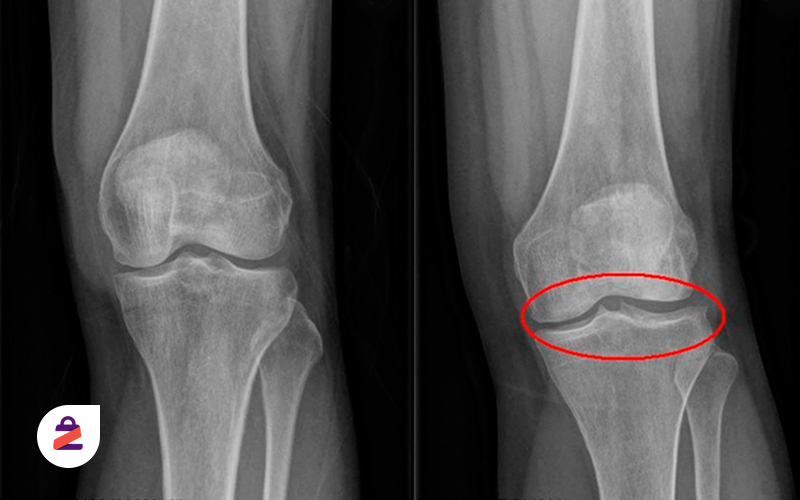

تصویر رادیولوژی از یک آرتروز زانو

3. تصویربرداری: انجام ایکس‌ری زانو می‌تواند به پزشک کمک کند تا تغییرات در ساختار زانو را مشاهده کند. در مواردی که نیاز به تشخیص دقیق‌تر است،ممکن است از روش‌های تصویربرداری پیشرفته‌تر مانند آندوسکوپی یا MRI استفاده شود.